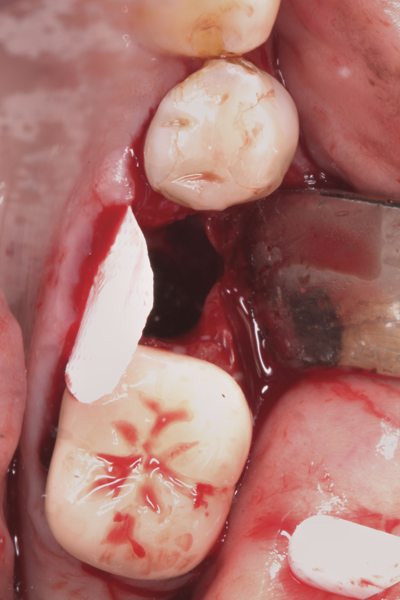

Fig 17. Bone graft was placed in the socket and a d-PTFE barrier was used to cover the graft. The bone graft material was placed beyond the alveolar housing to accommodate shrinkage of graft material and to facilitate attaining a wide alveolar ridge. The barrier was removed after 6 weeks.

Figure 17

Fig 18. Healed ridge exposed after 6 months.

Figure 18

Fig 19. Implant inserted into healed ridge.

Figure 19